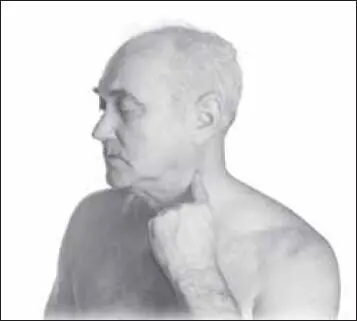

Проводим точечный самомассаж области шеи. Массируем точку фу-ту (расположена на середине грудинно-ключично-сосцевидной мышцы, на уровне верхнего края щитовидного хряща) (рис. 120). Воздействие седативное, расслабляющее, тормозящее, успокаивающее (до 1–2 минут), проводится на стороне патологии.